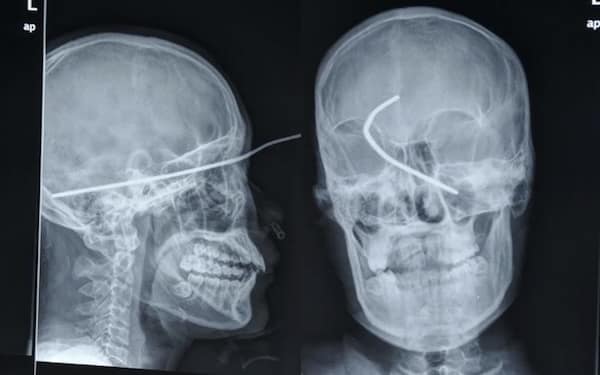

Weird xray photos

I used to think that nothing could surprise me anymore—until I stumbled upon some weird x-ray photos that made me reconsider my stance on human ingenuity (or lack thereof). Apparently, some people have a knack for getting objects lodged where they absolutely shouldn’t be. If you’ve ever wondered how not to use everyday items, these images might provide some unintended guidance.

This collection showcases 31 bizarre x-ray images that defy logic and anatomy textbooks alike. Each photo reveals unexpected objects making cameo appearances inside the human body, turning medical imaging into a gallery of the absurd. From common household items inexplicably found in unusual places to anomalies that would leave even seasoned doctors scratching their heads, these images offer a perplexing glimpse into the more “creative” side of medical emergencies. They highlight the intersection of curiosity, misadventure, and perhaps a dash of poor decision-making, all captured through the lens of radiology.